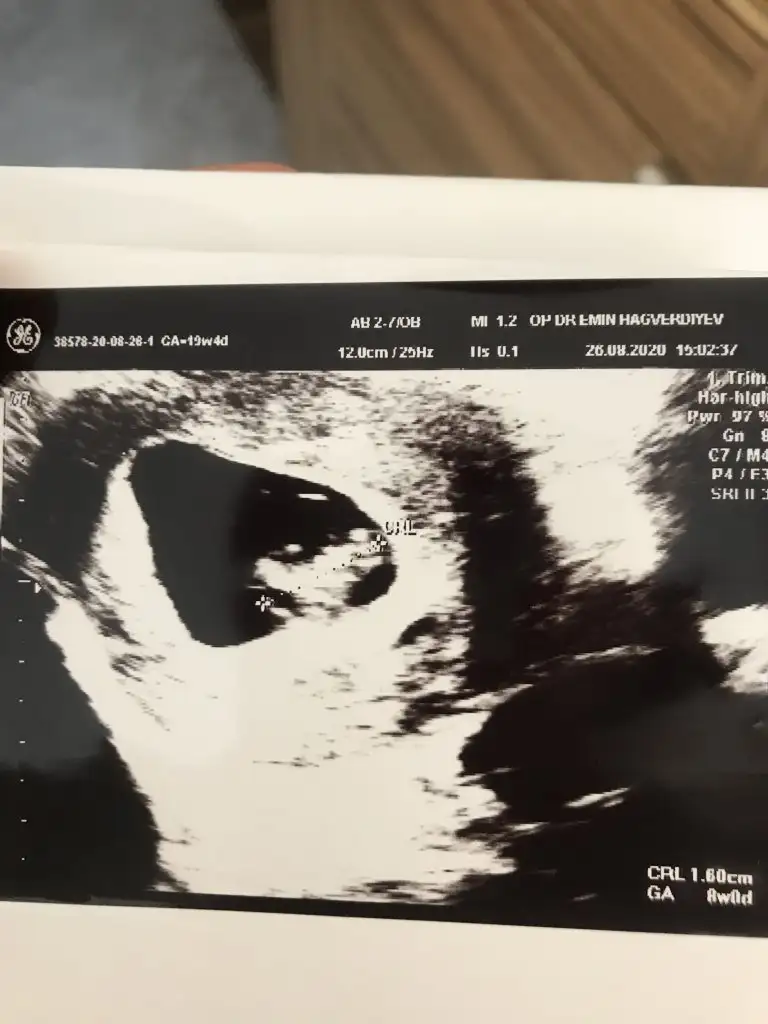

Bende kız hissediyorum bakalım ne çıkacakKız buna göre tabiki en iyi 11 12 13 haftalar olmalı

Kız gibi buna göreÇok teşekkür ederim. Aynı gün çekilmiş bir usg daha var. Orda da sağa yakın görünüyor.

Kese için büyük nub için küçük 11 12 13 haftalar olmalı9 haftalık resim ikra meyra yorumlayabilirmisiniz cinsiyetini:)